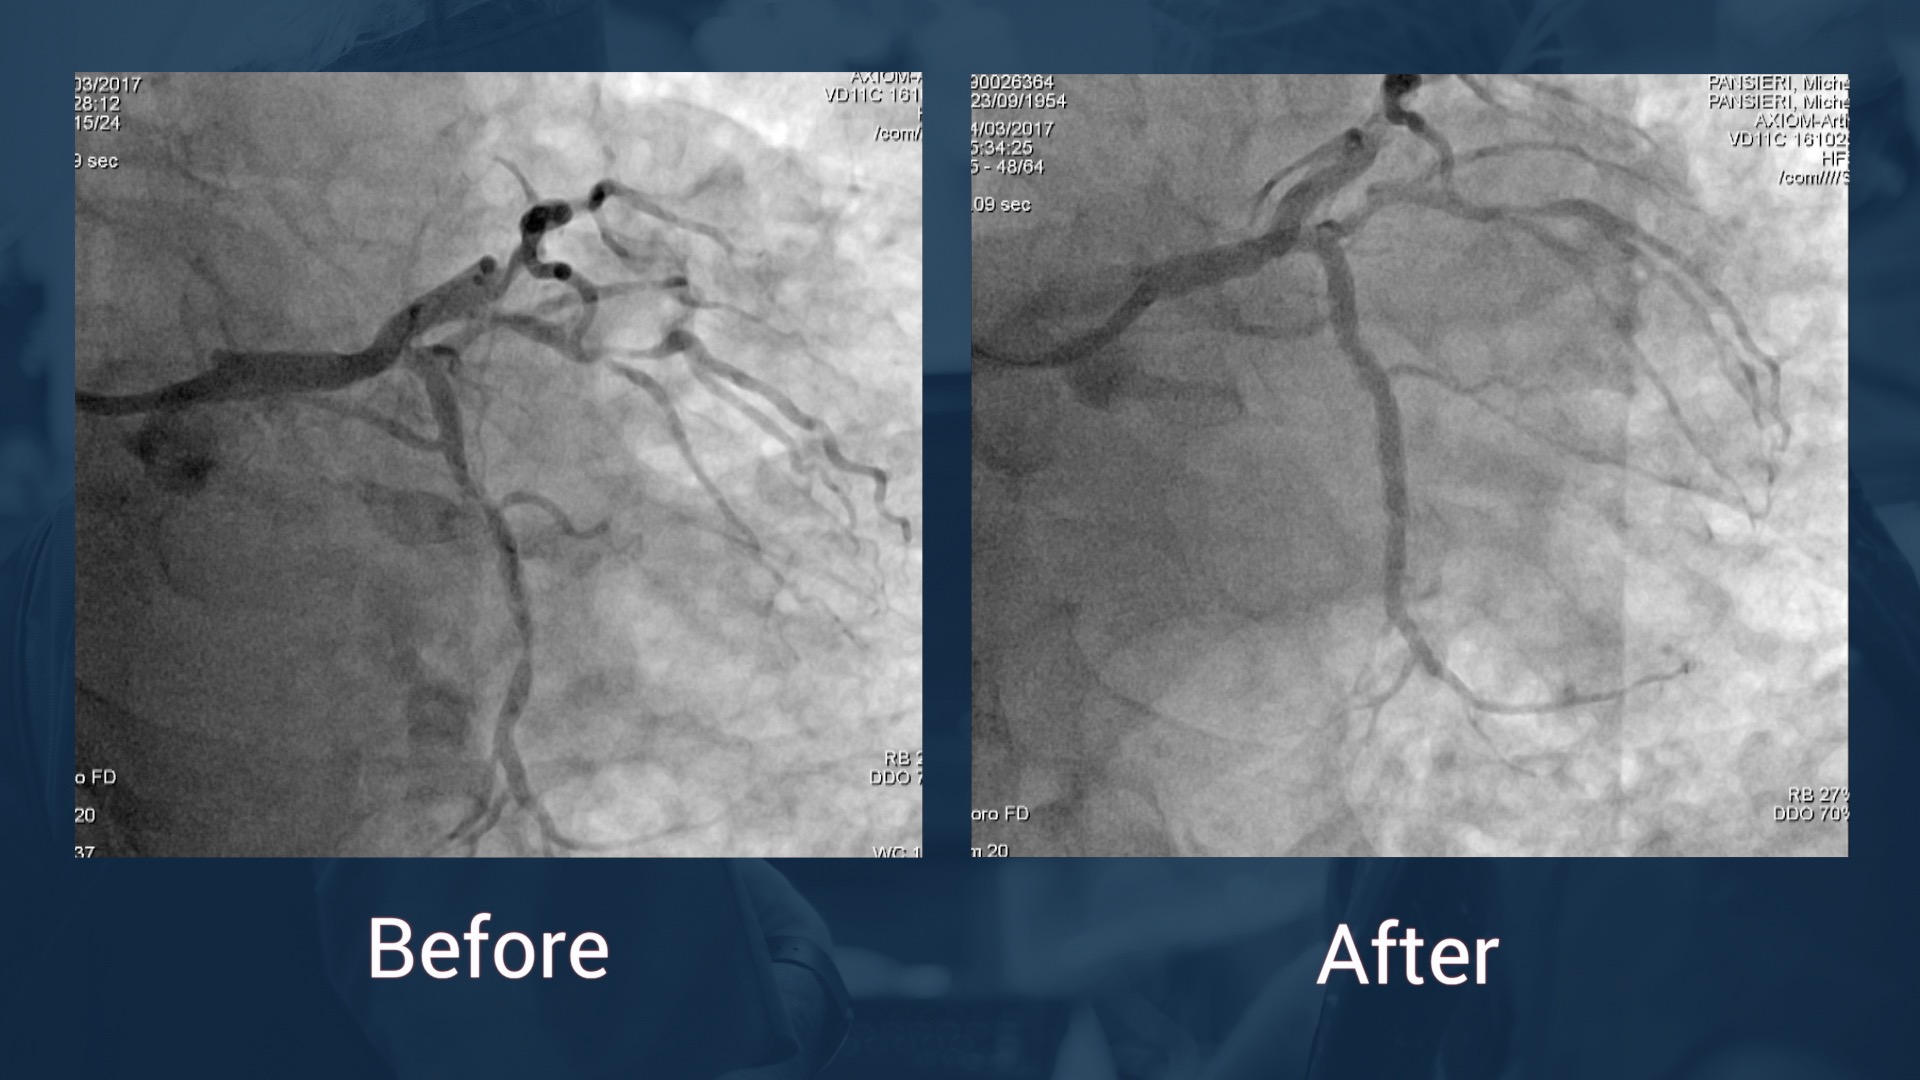

Left main coronary stenting by polymer free stent. OCT evaluation

76 year old patient diagnosed with a severe aortic stenosis.

The coronary angiography reveals a severe left main trunk stenosis on its distal part and an intermediate stenosis of the proximal part of the left anterior descending artery.